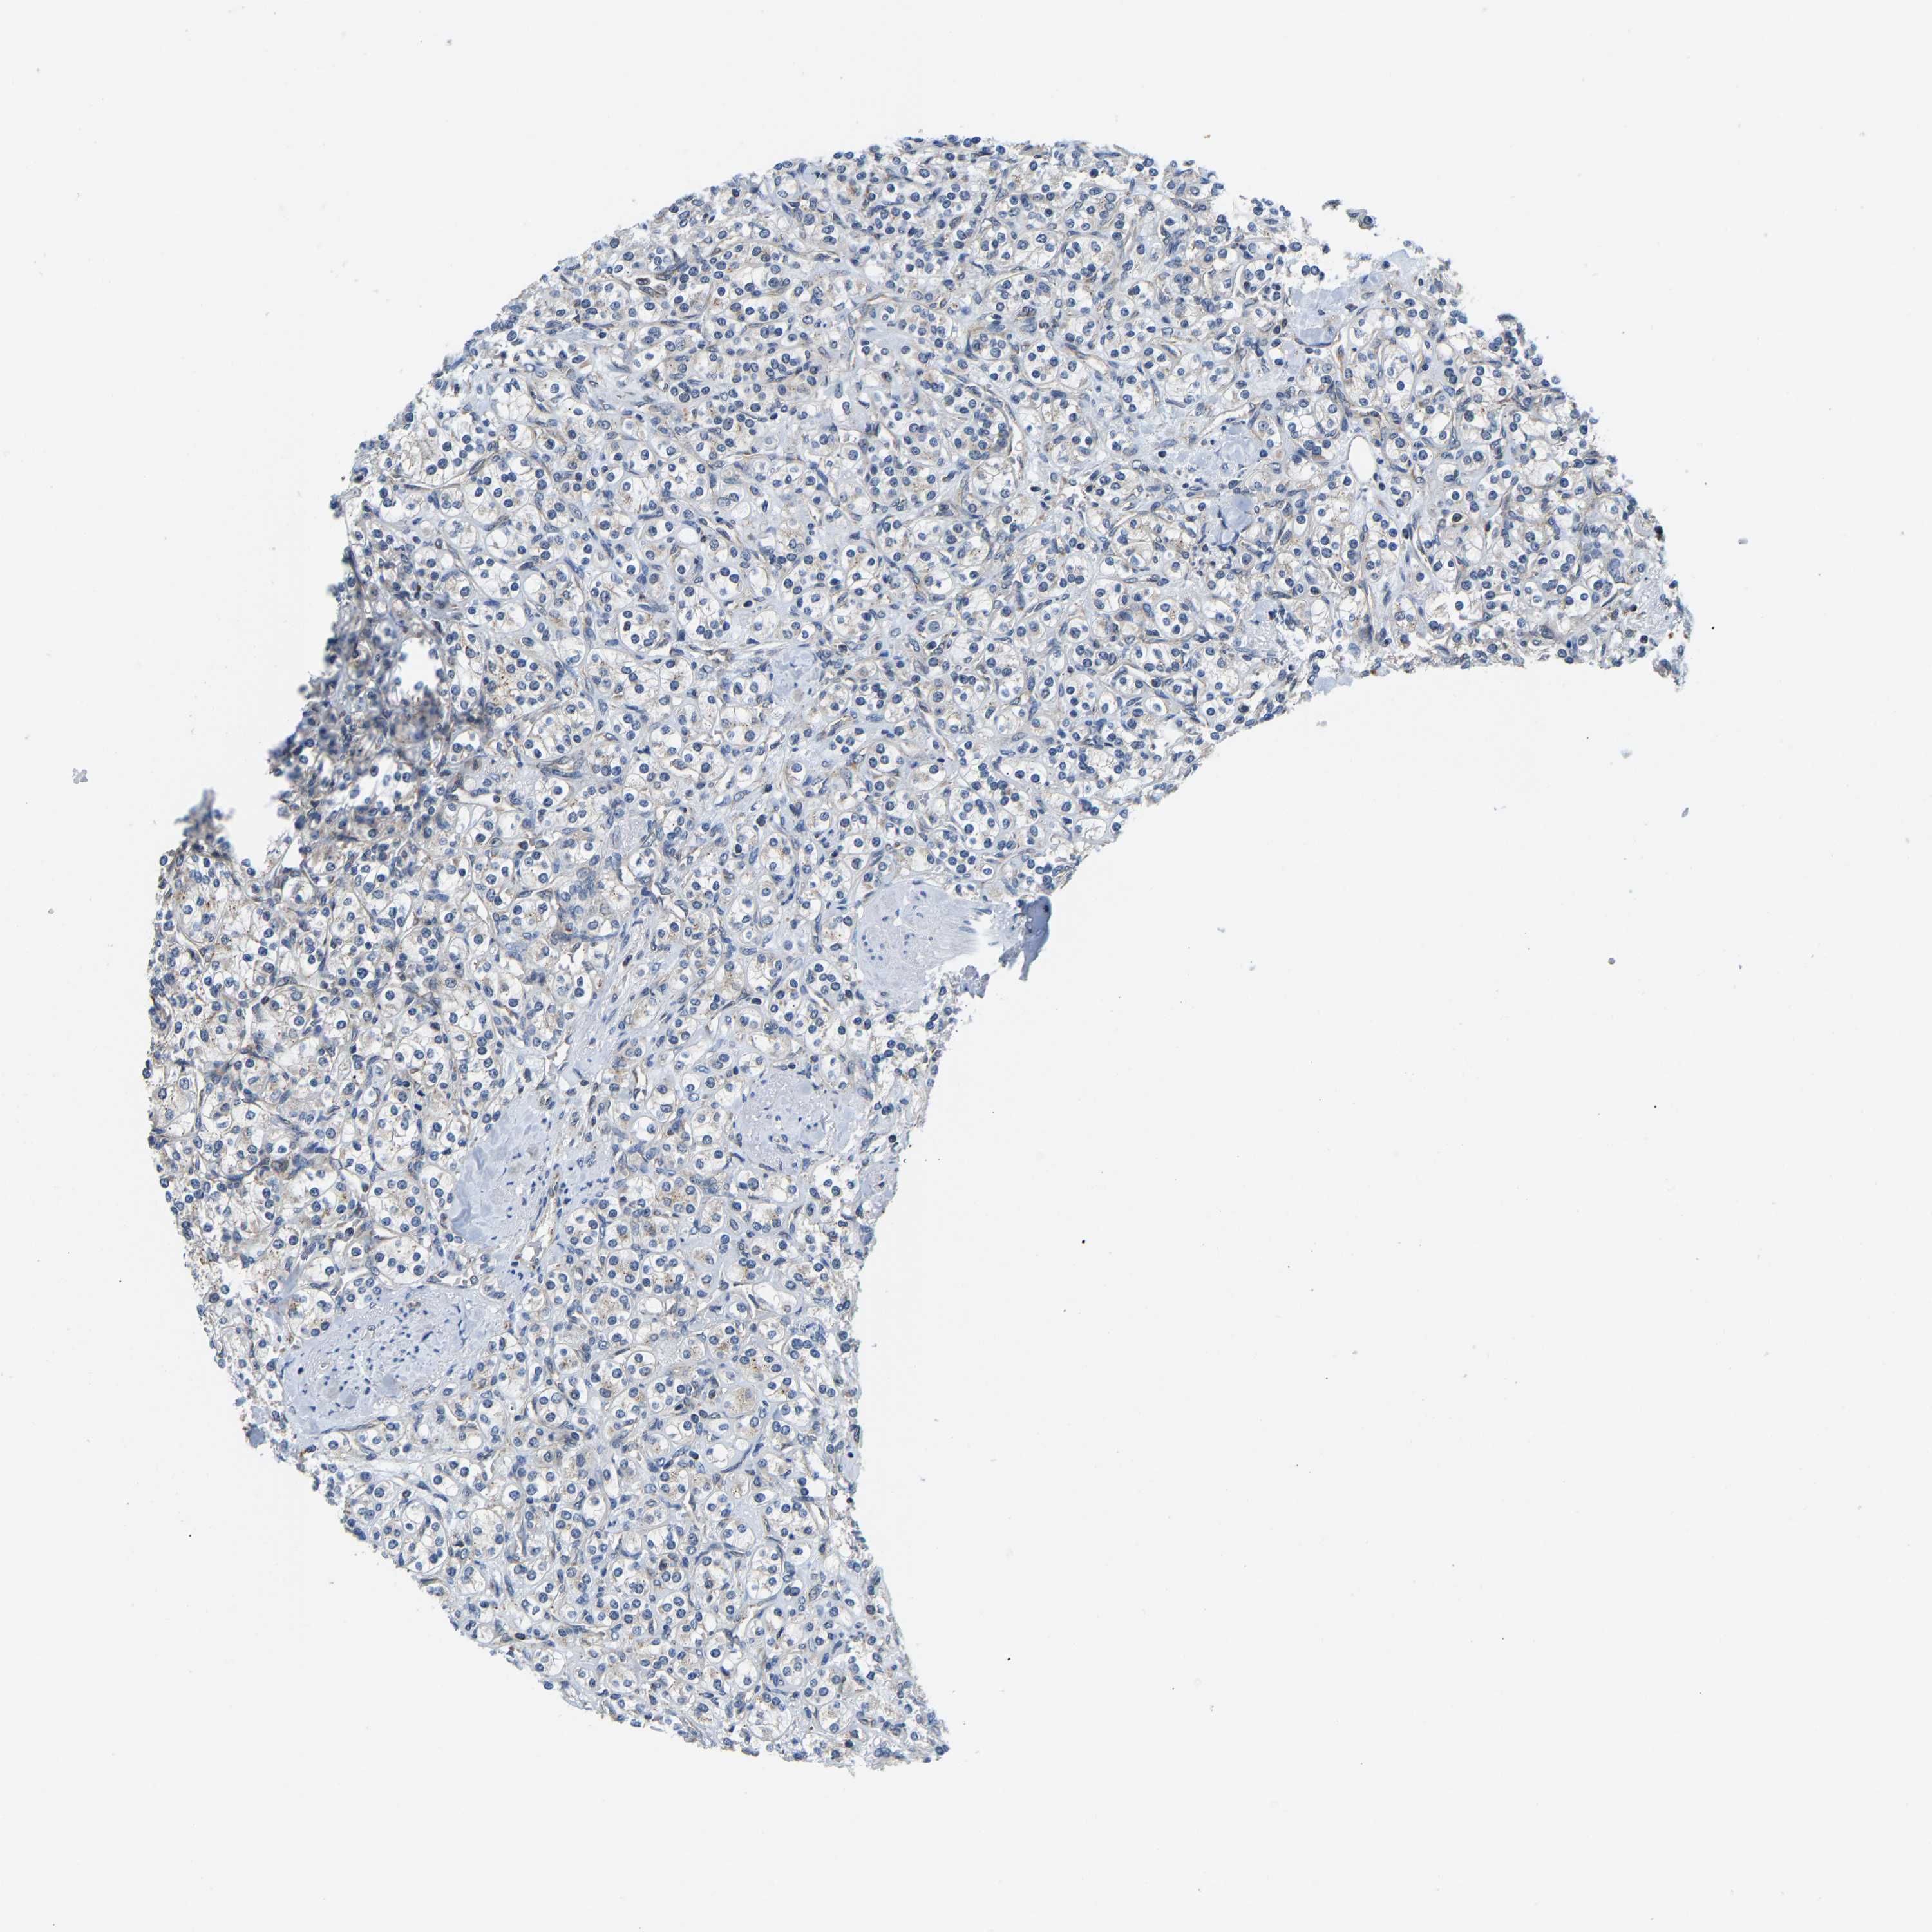

KIDNEY RENAL PAPILLARY CELL CARCINOMA (TCGA) - Interactive survival scatter ploti

The Survival Scatter plot shows the clinical status (i.e. dead or alive) for all individuals in the patient cohort, based on the same data that underlies the corresponding Kaplan-Meier plots. Patients that are alive at last time for follow-up are shown in blue and patients who have died during the study are shown in red.

The x-axis shows the expression levels (FPKM) of the investigated gene in the tumor tissue at the time of diagnosis. The y-axis shows the follow-up time after diagnosis (years). Both axes are complimented with kernel density curves demonstrating the data density over the axes. The top density plot shows the expression levels (FPKM) distribution among dead (red) and alive patients (blue). The right density plot shows the data density of the survived years of dead patients with high and low expression levels respectively, stratified using the cutoff indicated by the vertical dashed line through the Survival Scatter plot. This cutoff is automatically defined based on the FPKM cutoff that minimizes the p-score. The cutoff can be changed by dragging the vertical line or by entering a cutoff value in the square labeled "Current cut-off".

Under the Survival Scatter plot the p-score landscape (black curve; left axis) is shown together with dead median separation (red curve; right axis). Dead median separation is the difference in median mRNA expression between patients who have died with high and low expression, respectively. It is calculated as follows: median FPKM expression of dead patients with high expression - median FPKM expression of dead patients with low expression. This is intended to aid the user in visually exploring custom cutoffs and the associated p-scores and dead median separation.

Individual patient data is displayed and can be filtered by clicking on one or more of the category buttons on the top of the page. Categories describing expression level and patient information include: high, low, alive, dead, female, male and tumor stages. The scale of the x-axis can be toggled between linear and log-scale by clicking on the "x log" button. Mouse-over function shows TCGA ID, patient information and mRNA expression (FPKM) for each patient.

& Survival analysisi

Kaplan-Meier plots summarize results from analysis of correlation between mRNA expression level and patient survival. Patients were divided based on level of expression into one of the two groups "low" (under cut off) or "high" (over cut off). X-axis shows time for survival (years) and y-axis shows the probability of survival, where 1.0 corresponds to 100 percent.

GIMAP7 is not prognostic in Kidney Renal Papillary Cell Carcinoma (TCGA)